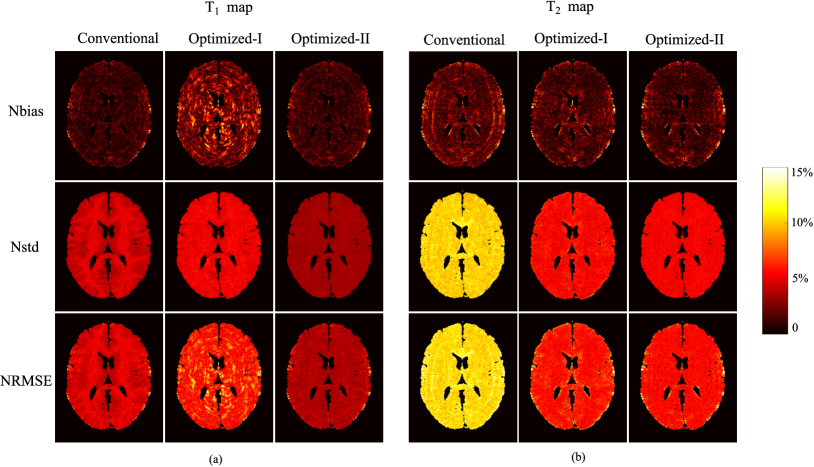

Figure 6: Bias-variance analysis of the reconstructed parameter maps from the fully-sampled MR fingerprinting experiments (N=400𝑁400N=400 and SNR=33dBSNR33dB\mathrm{SNR}=33~{}\mathrm{dB}), using the acquisition parameters from the conventional scheme, Optimized-I, and Optimized-II. (a) Normalized bias, standard deviation, and root-mean-square error for (a) T1subscript𝑇1T_{1} maps and (b) T2subscript𝑇2T_{2} maps. The regions associated with the background, skull, scalp, and CSF were set to be zero.

We further investigated the bias-variance property of the reconstructed parameter maps. Specifically, we performed Monte Carlo (MC) simulations with 100 trials to calculate the bias, standard deviation, and root-mean-square error of the reconstructed parameter maps. For convenience, we normalized these quantities as follows: (1) normalized bias:

Nbiasv=𝔼^[|𝐈v𝐈^v|]/𝐈v,subscriptNbias𝑣^𝔼delimited-[]subscript𝐈𝑣subscript^𝐈𝑣subscript𝐈𝑣\text{Nbias}_{v}=\hat{\mathbb{E}}\left[\left|\mathbf{I}_{v}-\hat{\mathbf{I}}_{v}\right|\right]/\mathbf{I}_{v}, (18)

(2) normalized standard deviation:

Nstdv=𝔼^[|𝐈^vE^(𝐈^v)|2]/𝐈v,subscriptNstd𝑣^𝔼delimited-[]superscriptsubscript^𝐈𝑣^Esubscript^𝐈𝑣2subscript𝐈𝑣\text{Nstd}_{v}=\sqrt{\hat{\mathbb{E}}\left[\left|\hat{\mathbf{I}}_{v}-\hat{\text{E}}(\hat{\mathbf{I}}_{v})\right|^{2}\right]}/\mathbf{I}_{v}, (19)

and (3) normalized root-mean-square error:

NRMSEv=𝔼^[|𝐈v𝐈^v|2]/𝐈v,subscriptNRMSE𝑣^𝔼delimited-[]superscriptsubscript𝐈𝑣subscript^𝐈𝑣2subscript𝐈𝑣\text{NRMSE}_{v}=\sqrt{\hat{\mathbb{E}}\left[\left|\mathbf{I}_{v}-\hat{\mathbf{I}}_{v}\right|^{2}\right]}/\mathbf{I}_{v}, (20)

where 𝔼^()^𝔼\hat{\mathbb{E}}(\cdot) denotes the empirical mean evaluated for the MC simulations, and 𝐈vsubscript𝐈𝑣\mathbf{I}_{v} and 𝐈^vsubscript^𝐈𝑣\hat{\mathbf{I}}_{v} respectively denote the v𝑣vth voxel from the true parameter map and reconstructed parameter map. Note that

NRMSEv=Nbiasv2+Nstdv2.subscriptNRMSE𝑣superscriptsubscriptNbias𝑣2subscriptsuperscriptNstd2𝑣\text{NRMSE}_{v}=\sqrt{\text{Nbias}_{v}^{2}+\text{Nstd}^{2}_{v}}.

Fig. 6 shows the normalized bias, standard deviation, and root-mean-square error maps for the reconstructed T1subscript𝑇1T_{1} and T2subscript𝑇2T_{2} maps. As can be seen, Optimized-I and Optimized-II reduce the normalized standard deviations for both T1subscript𝑇1T_{1} and T2subscript𝑇2T_{2}, compared to the conventional scheme. Consistent with the CRB prediction and the results shown in Fig. 5, the improvement for T2subscript𝑇2T_{2} is more substantial than for T1subscript𝑇1T_{1}. Moreover, for all three acquisition schemes, the normalized standard deviation is much larger than the normalized bias, and the normalized root-mean-square error is dominated by the normalized standard deviation. The above behavior can be expected, given that the ML reconstruction is asymptotically unbiased [14].

Figure 10: Bias-variance analysis of the reconstructed parameter maps from the highly-undersampled MR fingerprinting experiments (N=400𝑁400N=400 and SNR=33dBSNR33dB\mathrm{SNR}=33~{}\mathrm{dB}), using the acquisition parameters from the conventional scheme, Optimized-I, and Optimized-II. (a) Normalized bias, standard deviation, and root-mean-square error for (a) T1subscript𝑇1T_{1} maps and (b) T2subscript𝑇2T_{2} maps. The regions associated with the background, skull, scalp, and CSF were set to be zero.

III-A5 Evaluation of highly-undersampled experiments

We repeated the same evaluations but applied to the highly-undersampled case. Note that this more closely matches the way that MR fingerprinting is applied in practice. Fig. 9 shows the reconstructed T1subscript𝑇1T_{1} and T2subscript𝑇2T_{2} maps from the highly-undersampled experiments at N=400𝑁400N=400 and SNR=33SNR33\mathrm{SNR}=33 dB, using the conventional scheme, and the two optimized schemes. As can be seen, Optimized-I improves the accuracy of the T2subscript𝑇2T_{2} map over the conventional scheme, but at the expense of degrading the accuracy of the T1subscript𝑇1T_{1} map. In contrast, Optimized-II provides better accuracy for both T1subscript𝑇1T_{1} and T2subscript𝑇2T_{2} maps, which is highly desirable. Note that the ML reconstruction involves solving a nonlinear and nonconvex optimization problem, for which a good initialization is often required. By enforcing the additional constraint on the flip angle variations, Optimized-II results in much smoother magnetization evolutions (as shown in Fig. 3). With the highly-undersampled data, this often leads to better pattern matching results for the conventional reconstruction, which in turn provides an improved initialization for the ML reconstruction.

Fig. 10 shows the normalized bias, standard deviation, and root-mean-square error maps for the reconstructed T1subscript𝑇1T_{1} and T2subscript𝑇2T_{2} maps from the MC simulations (with 100 trials). Clearly, Optimized-II reduces the normalized standard deviation and root-mean-square error for both T1subscript𝑇1T_{1} and T2subscript𝑇2T_{2} maps, compared to the conventional scheme. Moreover, with smooth magnetization evolutions, Optimized-II reduces the bias compared to Optimized-I. This further illustrates the merit of introducing the constraint on the flip angle variations for the highly-undersampled experiments.